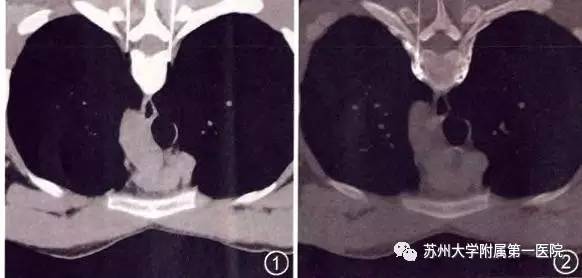

术前准备充分后,小玉被推入CT室,金主任在CT下定位需要穿刺阻断的胸交感神经的位置。

精确定位后开始双针穿刺,注入造影剂及试验剂量局麻药,不到5分钟,小玉原本如浸湿在水里的双手开始变得干爽、温度也逐渐上升,并没有其他不适反应,CT显示药物扩散位置十分安全满意。

15分钟等造影剂充分扩散吸收后,注入神经毁损药永久阻断相应胸交感神经。